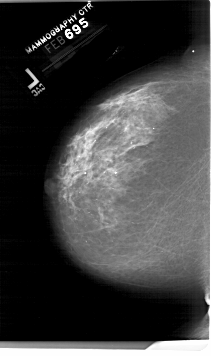

A_1999_1.LEFT_MLO

LEFT_MLO LINES 6346 PIXELS_PER_LINE 4246 BITS_PER_PIXEL 12 RESOLUTION 43.5 NON_OVERLAY